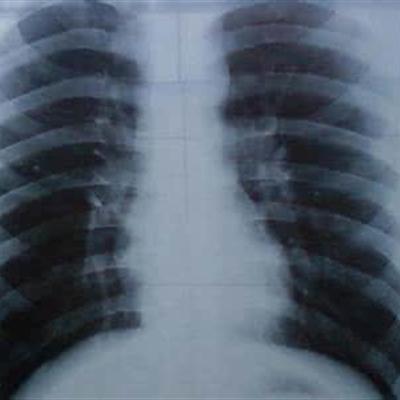

Second: long term low fever is one of the early symptoms of lung cancer. After blocking the bronchus, there are often obstructive pulmonary lobes with different degrees. Mild patients have only low fever, severe patients have high fever. After treatment, they can be temporarily improved, but they will relapse very quickly.